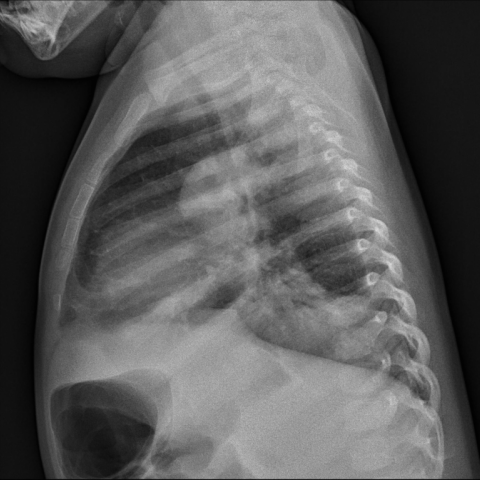

侧位胸片显示左下叶局部肺不张及实变,肺门内有气体